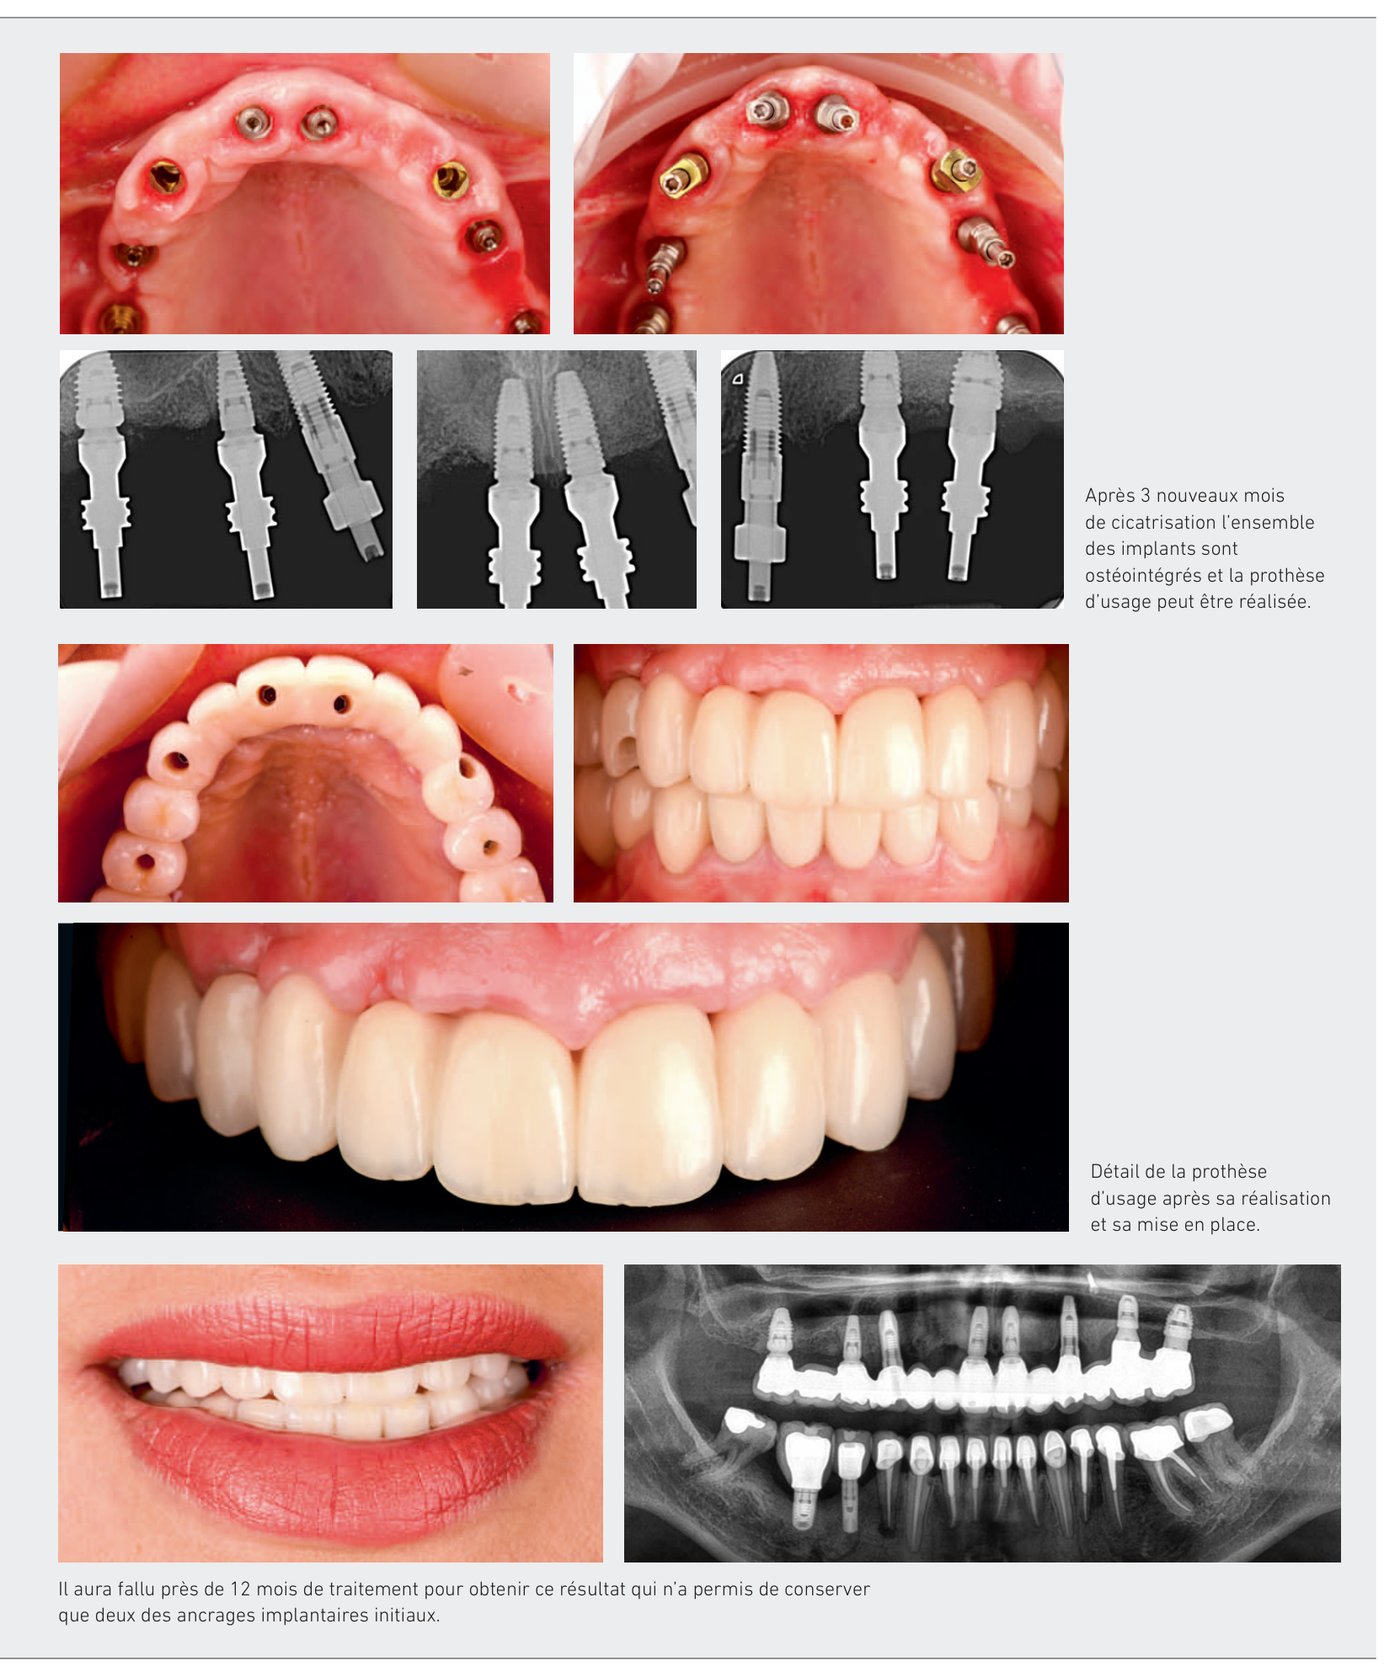

Il aura fallu près de 12 mois de traitement pour obtenir ce résultat qui n'a permis de conserver que deux des ancrages implantaires initiaux.